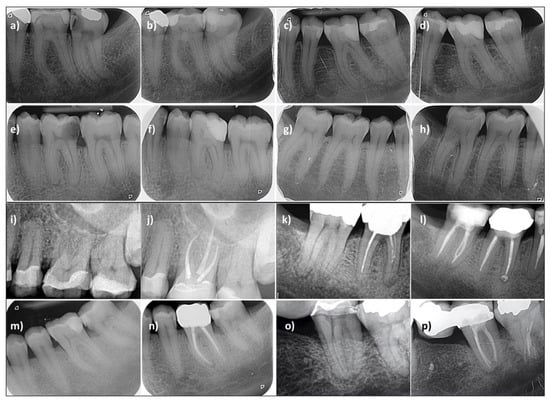

3.2. Treatment Success